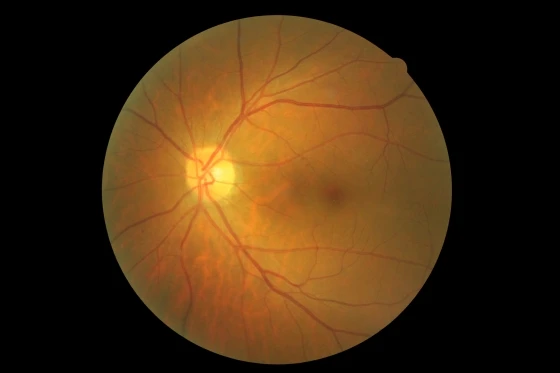

眼底攝影-BDR 背基型糖尿病視網膜病變

背基型糖尿病視網膜病變(background diabetic retinopathy, 簡稱:BDR)

紅點:微動脈瘤

白點:硬滲出物 紅點:微動脈瘤

白點:硬滲出物 紅點:微動脈瘤 大紅點:點狀出血